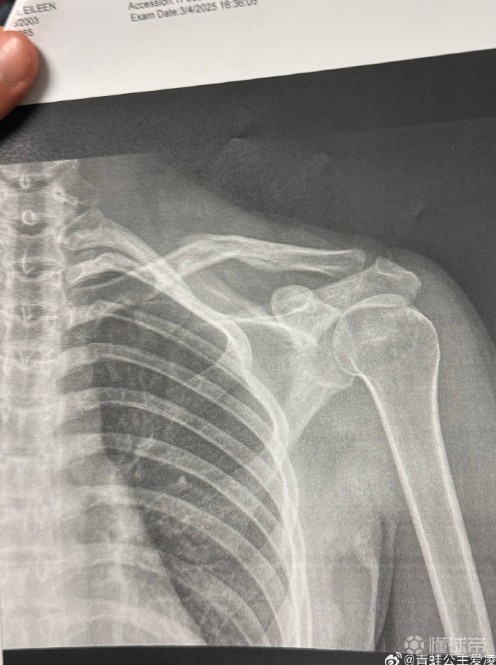

新伤还是旧伤?谷爱凌社媒晒骨折X光照片,上个月因伤退出亚冬会南京伦敦体育场小杨 @懂球帝2025-03-09 09:42北京时间3月9日,谷爱凌晒骨折X光照,并配了一个心碎的表情💔。从图片上看,片子的日期是3月4日,目前尚不得知谷爱凌本次的伤病是新伤还是旧伤。上个月谷爱凌在训练中不幸再次受伤,宣布不得不退出亚冬会。展开更多